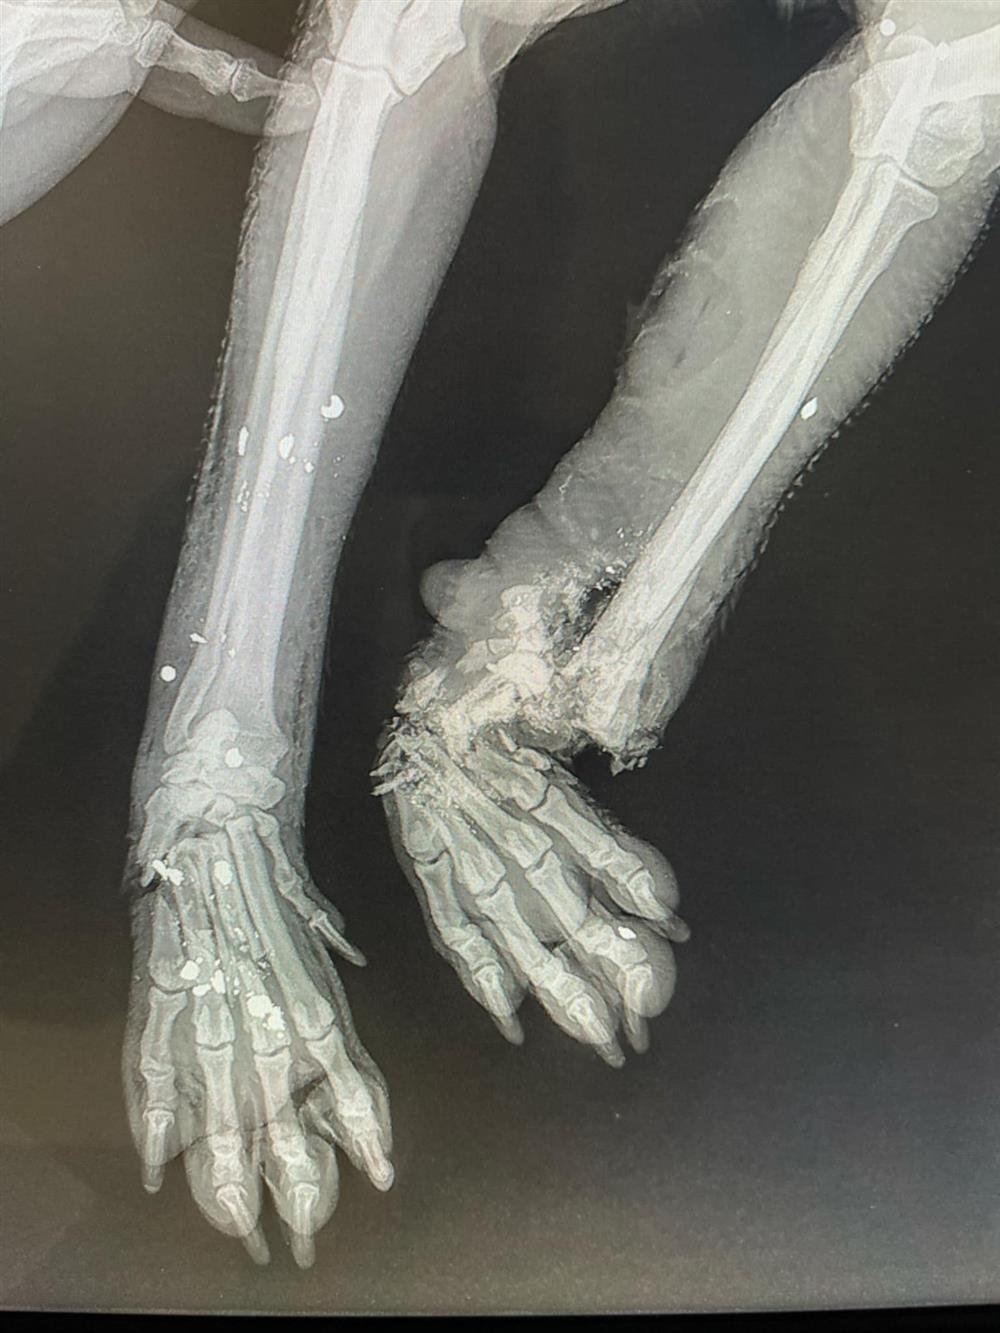

Ένα αποτρόπαιο περιστατικό κακοποίησης ζώου σημειώθηκε στο Αρκαλοχώρι του Δήμου Μινώα Πεδιάδας, στο Ηράκλειο, προκαλώντας σοκ και αγανάκτηση. Σύμφωνα με πληροφορίες, άγνωστος δράστης φέρεται να επιτέθηκε σε ένα μικρόσωμο σκυλάκι, προκαλώντας του σοβαρά τραύματα στα άκρα. Σαν να μην έφτανε αυτό, στη συνέχεια το πυροβόλησε, ολοκληρώνοντας την αποτρόπαια πράξη του.

Οι κτηνίατροι δεν κατάφεραν να σώσουν το ένα πόδι της σκυλίτσας, με αποτέλεσμα να προχωρήσουν σε ακρωτηριασμό, ενώ της τοποθέτησαν και νάρθηκα. Περαστικοί το βρήκαν στην άκρη του δρόμου να ουρλιάζει από τους φρικτούς πόνους.